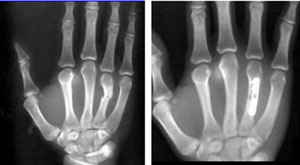

This X-ray shows a fracture in the middle of one of the bones of the finger.

Reproduced with permission from Kozin SH, Thoder JJ, Lieberman G: Operative Treatment of Metacarpal and Phalangeal Shaft Fractures. J Am Acad Orthop Surg 2000;8:111-121.